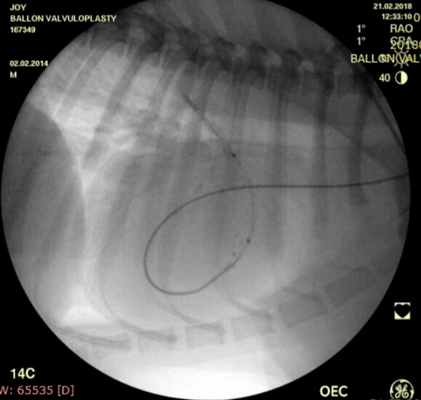

Проведено: баллонная вальвулопластика клапана легочной артерии (Тип А). Баллон Cordis maxi 40х20 мм. Инфляция до 5 атм. 10 попыток.

ЭхоКГ (после операции): ГД (градиент давления) на ЛА (легочной артерии) - 39 мм.рт.ст. РКЛА (регургитация клапана легочной артерии) – ср. - 16 мм рт.ст. Геометрия сердца не нарушена. Выраженное снижение градиента давления после баллонной дилатации КЛА (клапана легочной артерии) на 55%.